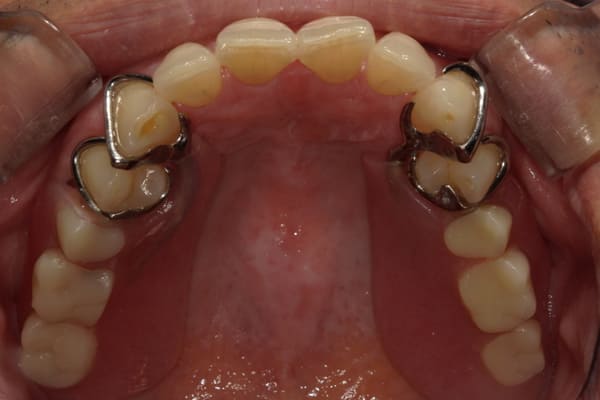

症例レポート[CASE.02]

- 男性(60代)

- 入れ歯がカパカパする、歯がぐらぐらして痛い、食いしばれない

- 治療

- 上顎精密総金属床総入れ歯

- 下顎精密金属床部分入れ歯

- ジルコニアクラウン4歯

- 治療期間

-

- 上顎精密総金属床総入れ歯:55万円

- 下顎精密金属床部分入れ歯:55万円

(ミリング、ラベット加工込み) - ジルコニアクラウン:11万円×4歯

合計:154万円(税込)

上の前歯が重度歯周病により動揺し、残せない状態のため、入れ歯も動揺がありました。

ご自身の歯に負担の少ないバネ、また見た目も改善

ご自身の歯に負担の少ないバネ

銀歯からセラミック歯に

バネをかける歯は繋げることで強度を増し、歯への負担を軽減し、歯の寿命を長くする設計へ。

バネがかかる歯の被せ物は、歯への負担を減らし、入れ歯が動きにくいようになる形態をあらかじめ付与することで、より入れ歯の機能が高まります。

治療を行う際、被せ物や入れ歯は、別々に考えるのではなく、一口腔単位としてお口全体のことを考え最良の治療計画を立てることが歯の寿命、機能効果を向上させるため、専門医としてこのことは常に心掛けて治療を行っています。

残りの歯に負担がかからないよう、被せ物と入れ歯の一体化を図った入れ歯

治療前は上下奥歯の入れ歯が削れていることで、かみ合わせが低くなり唇もつむった状態でした。

かみ合わせを適切な高さに戻したことで、本来の自然な口元へ。